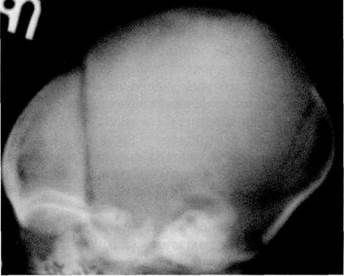

У новорожденного череп имеет долихоцефалическую форму, т. е. переднезадний размер головы преобладает над фронтальным и вертикальным. Различные варианты предлежания ребенка во время рождения влияют на форму его черепа. У детей, рожденных в головном предлежании, возникает своеобразная родовая конфигурация головы в виде более высокого стояния теменных костей по сравнению с чешуей лобной и затылочной костей, а также на-ползания теменных костей на лобную и затылочную. Это отчетливо видно на боковой кра-ниограмме, где имеется возвышенное положение теменных костей, а вместо прозрачных промежутков венечного и ламбдовидного швов появляются полосы суперпозиции (уплот­нения тени), обусловленные наслоением краев теменных костей на смежные края лобной и затылочной костей. На прямой рентгенограмме черепа теменные кости стоят симметрично, на одном уровне. У здорового ребенка не должно быть ни их разновысокого стояния, ни, тем более, взаимного захождения (рис. 2.1).

Рис. 2.1. Боковая краниограмма ребенка 5 дней, рожденного в головном предлежании.

Родовая конфигурация черепа: теменные ко­сти расположены выше лобной и затылочной костей. Венечный шов узкий, просвет ламб­довидного шва не визуализирован вследствие взаимного захождения костей.